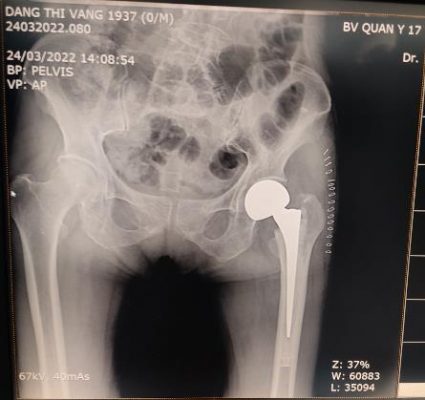

Khớp giả cổ xương đùi Thay khớp háng bán phần có xi măng